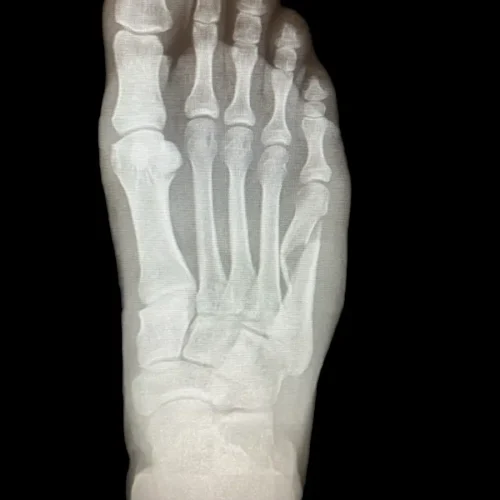

Surgical Intervention at Stepwell Institute is never a “one-size-fits-all” solution. We view surgery as a precise tool used to restore the natural biomechanics of the foot and ankle when non-invasive methods have reached their limit. Our philosophy centers on individualized surgical planning—using advanced imaging to map out the procedure before you ever enter the operating room. From correcting bunions and hammertoes to performing ligament repairs and fracture fixations, Dr. Yakov utilizes techniques designed to minimize trauma to the surrounding tissues, thereby reducing the risk of complications and ensuring a more stable, long-term result for our patients.

Knowing when to transition to surgical care at Stepwell Institute is a collaborative decision between you and Dr. Yakov. If you live in the New Jersey area, you should consider a surgical consultation if you experience persistent pain that has failed to respond to orthotics, injections, or physical therapy, or if a deformity is significantly limiting your mobility. Many of our patients seek surgical intervention for conditions that have become “rigid,” such as advanced arthritis or severe tendon tears, which cannot be managed with conservative tools alone. If your foot or ankle condition is preventing you from working, exercising, or enjoying daily life, a professional evaluation at Stepwell Institute is necessary to discuss your surgical options.